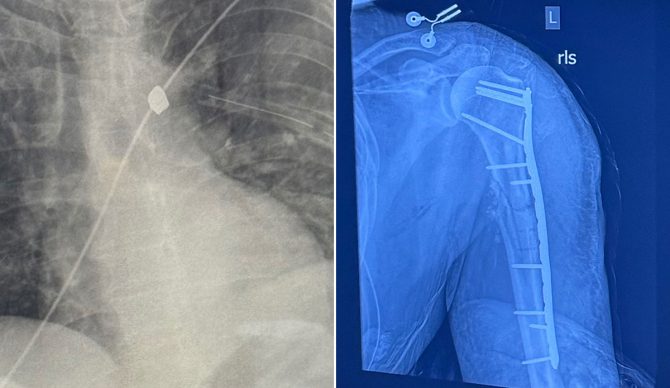

The bullet that hit Roberts went through his arm first, before hitting his ribs and shredding a lung. It just missed his aorta, which would have been a death sentence. His left arm was shattered and required metal plates to be held together. X-ray images shared by a GoFundMe campaign show the bullet lodged in his body. His friend was treated and released from the hospital.

X-rays show the plate attached to Roberts’ humerus bone and the bullet lodged near his aorta. Photos: GoFundMe